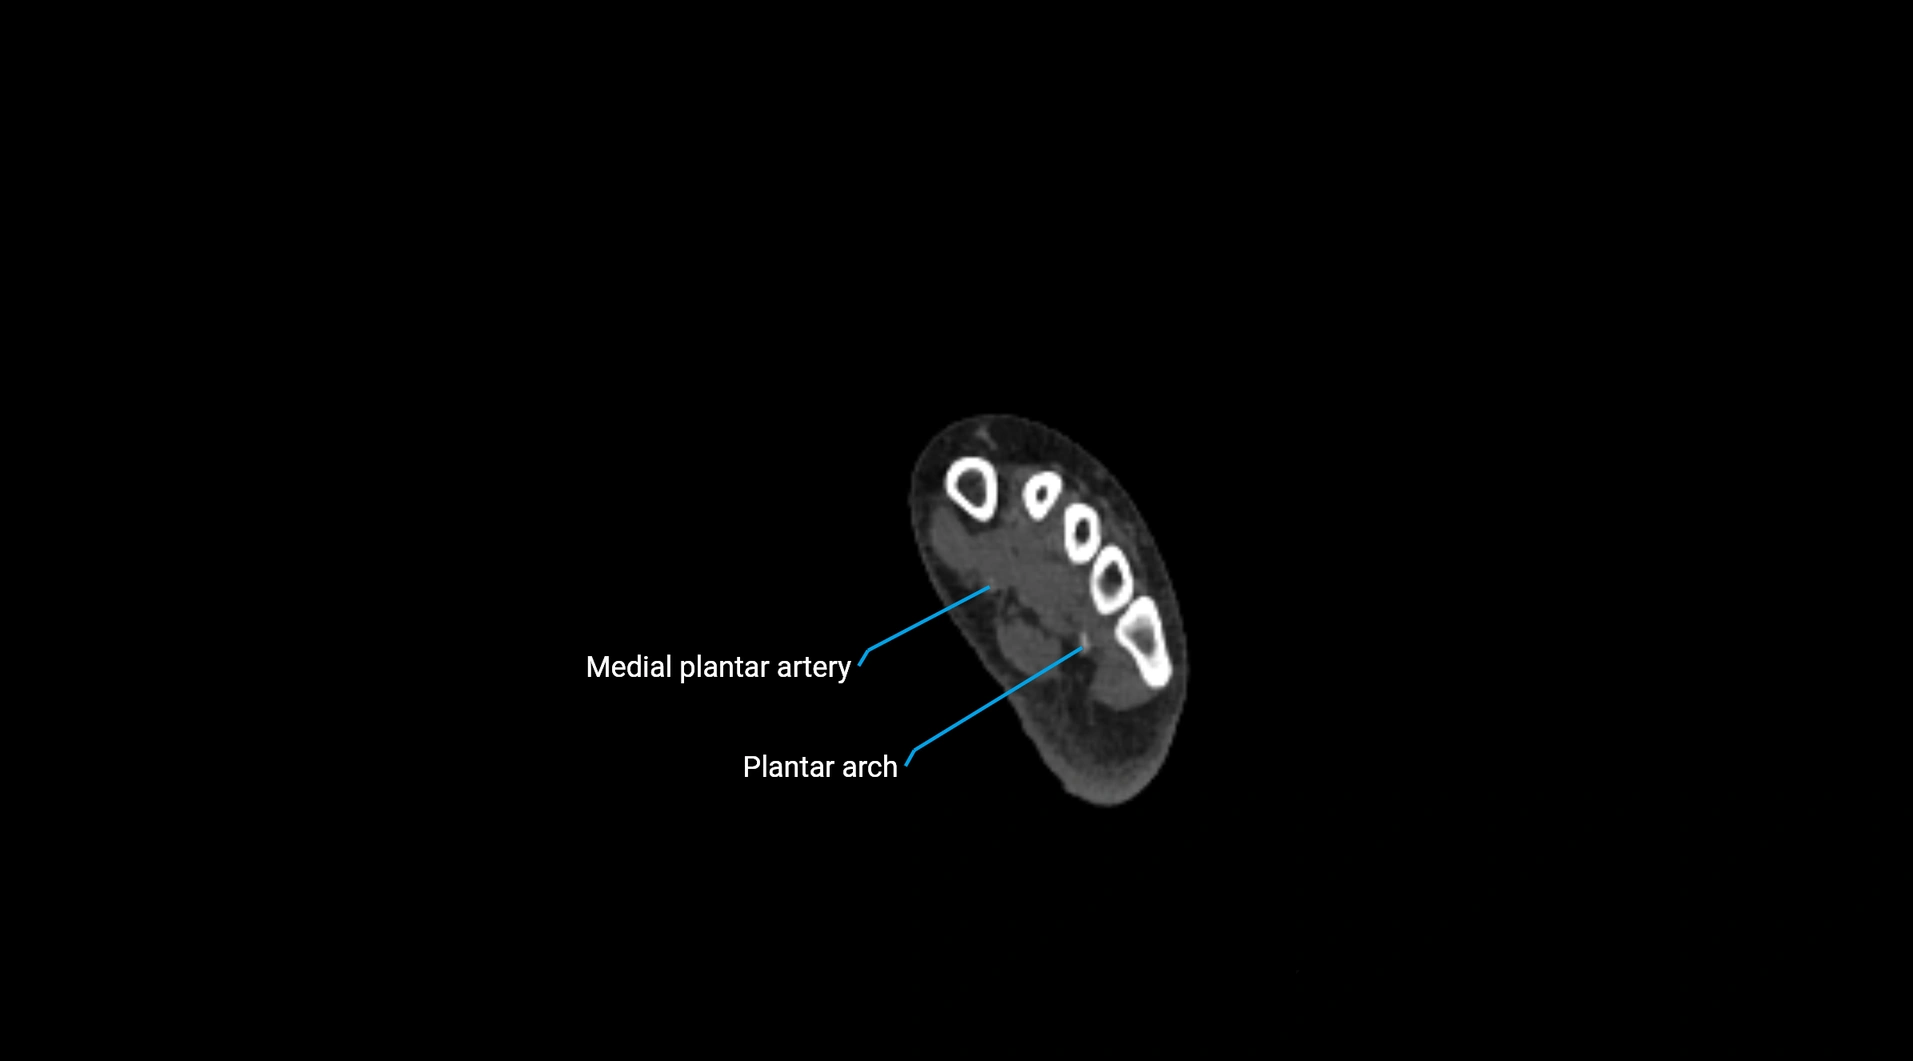

CT Appearance

Non-contrast CT:

• Appears as a tubular soft tissue structure anterior to vertebral bodies

• Calcified atherosclerotic plaques appear as hyperdense foci along the wall

• Useful for screening abdominal aortic aneurysm (AAA) size and mural calcification

Contrast-enhanced CT (CTA):

• Gold standard for abdominal aortic imaging

• Provides excellent detail of lumen, wall, aneurysm, thrombus, and branch vessels

• Multiplanar and 3D reconstructions help in aneurysm measurement, stent graft planning, and dissection evaluation

• Detects acute rupture, traumatic injury, or occlusion with high sensitivity

CT images

image